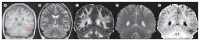

Brain imaging has a crucial role in the presurgical assessment of patients with epilepsy. Structural imaging reveals most cerebral lesions underlying focal epilepsy. Advances in MRI acquisitions including diffusion-weighted imaging, post-acquisition image processing techniques, and quantification of imaging data are increasing the accuracy of lesion detection. Functional MRI can be used to identify areas of the cortex that are essential for language, motor function, and memory, and tractography can reveal white matter tracts that are vital for these functions, thus reducing the risk of epilepsy surgery causing new morbidities. PET, SPECT, simultaneous EEG and functional MRI, and electrical and magnetic source imaging can be used to infer the localisation of epileptic foci and assist in the design of intracranial EEG recording strategies. Progress in semi-automated methods to register imaging data into a common space is enabling the creation of multimodal three-dimensional patient-specific datasets. These techniques show promise for the demonstration of the complex relations between normal and abnormal structural and functional data and could be used to direct precise intracranial navigation and surgery for individual patients.